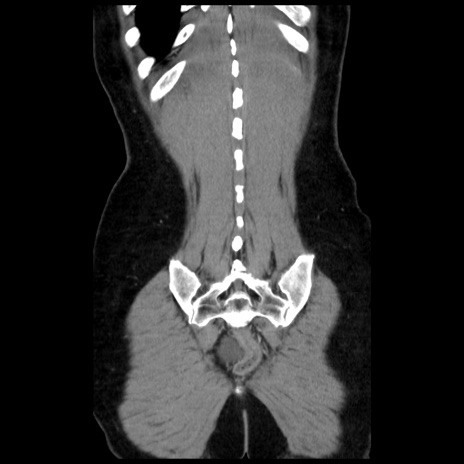

症例10(冠状断像)

【症例】 50歳代女性

【主訴】 腹痛

【現病歴】前日生レバーを食べた。今朝に排便あり。 昼前に突然発症の腹痛を生じ、当院救急外来を受診した。

【既往歴】 子宮筋腫にてで子宮全摘後

【身体所見】 意識清明、腹部:平坦、軟、下腹部やや左を中心に圧痛・反跳痛あり、筋性防御あり

【データ】WBC 7800、CRP 0.07